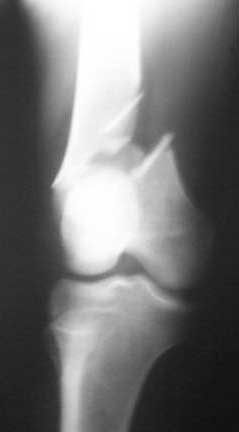

Images of knee and hips.

It's difficult to comment without quality films including the hip and knee.

Hip and knee normal. Will post the pictures at the earliest.